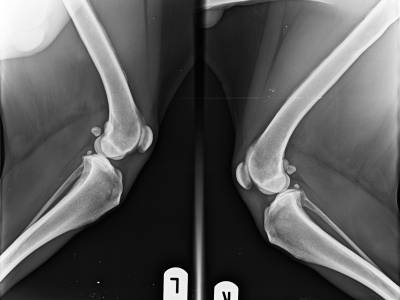

- bilaterale symmetrische periostale Knochenzubildungen an den Diaphysen der langen Röhrenknochen der Extremitäten

- Weichteilschwellung distal an den Extremitäten